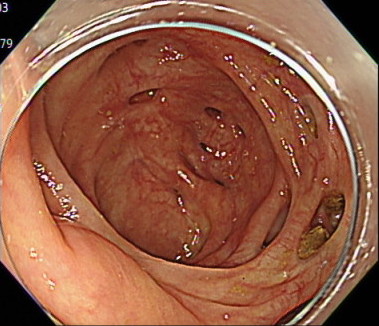

7. 先端フードを使用しないことで、広い視野を実現

「どんなに小さなポリープや変化も見逃さない」

大腸カメラでは、「先端フード」とよばれるカメラの先端につけるキャップのようなものがあります。

このキャップを内視鏡に装着することで、カメラの挿入がしやすくなるというメリットがあります。

しかし、周りの視野がせまくなるというデメリットがあります。

当クリニックでは、「軸保持短縮法」という挿入方法により。腸に負担なくスムーズな挿入を行うことで、先端アタッチメントなしでの大腸カメラ検査を実現しています。

これにより、広い視野での大腸の観察が可能となり、どんなに小さなポリープや変化も見逃さず、患者様に安心を提供できるよう尽力しております。

(※出血量が多い場合は、出血部位を特定しやすくするために、あらかじめ先端アタッチメントを装着して検査を行います。)

盲腸の観察(先端フードあり)

盲腸の観察(先端フードなし)

直腸の観察(先端フードあり)

直腸の観察(先端フードなし)